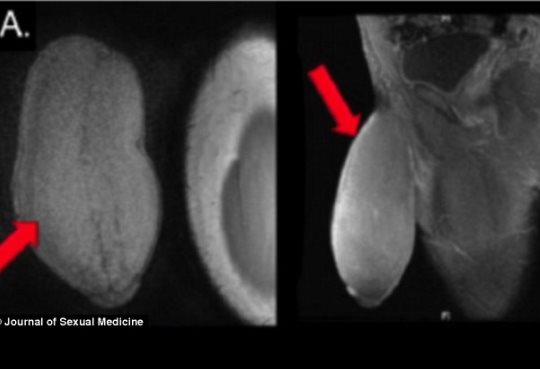

Σε επέμβαση συρρίκνωσης πέους υπεβλήθη ένας Αμερικανός 17χρονος έφηβος επειδή το γεννητικό του όργανο ήταν υπερβολικά μεγάλο και τον εμπόδιζε να κάνει σεξ και να συμμετέχει σε ορισμένα αθλήματα.

Το πέος του έφηβου είχε διάμετρο 25 εκατοστά και μήκος 17 εκατοστά. Οι χειρουργοί του περιγράφουν το σχήμα του σαν μια μπάλα αμερικανικού fotball.

Οι χειρουργοί δεν έκαναν τις τελικές μετρήσεις στο πέος του, παρόλο που ο ουρολόγος Δρ. Καρριόν δήλωσε ότι το αποτέλεσμα ήταν "γενναιόδωρο". parapolitika